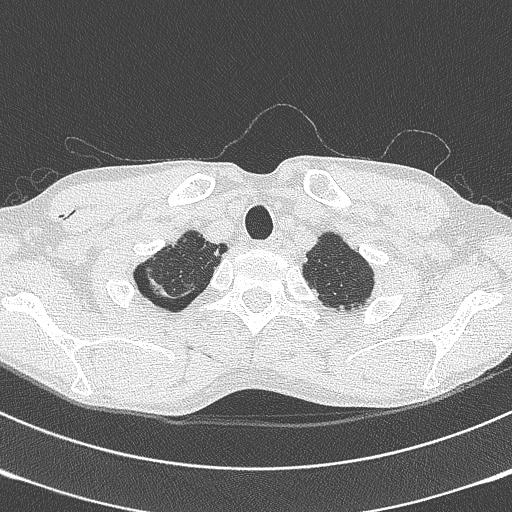

마지막으로 퇴원 전 F/U으로 찍은 CT입니다.

아직까지 조금의 흔적이 있네요. 며칠 전 촬영한 CT엔 거의 없어졌지만...

그림의 우측은 정상적이 폐조직이고 좌측(원래는 오른쪽 폐)의 아래 검은 부분이 기흉의 흔적입니다.